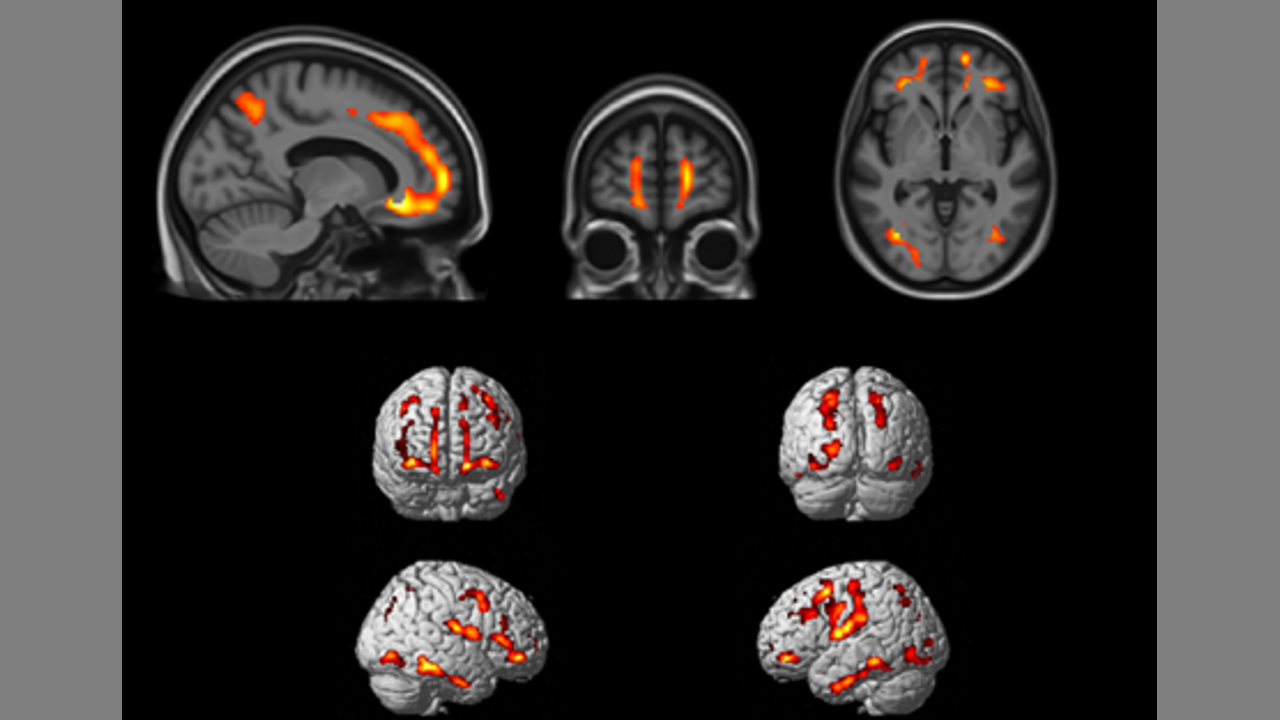

Mapping Brain Changes in Post-Covid-19 Cognitive Decline via FDG PET Hypometabolism and EEG Slowing